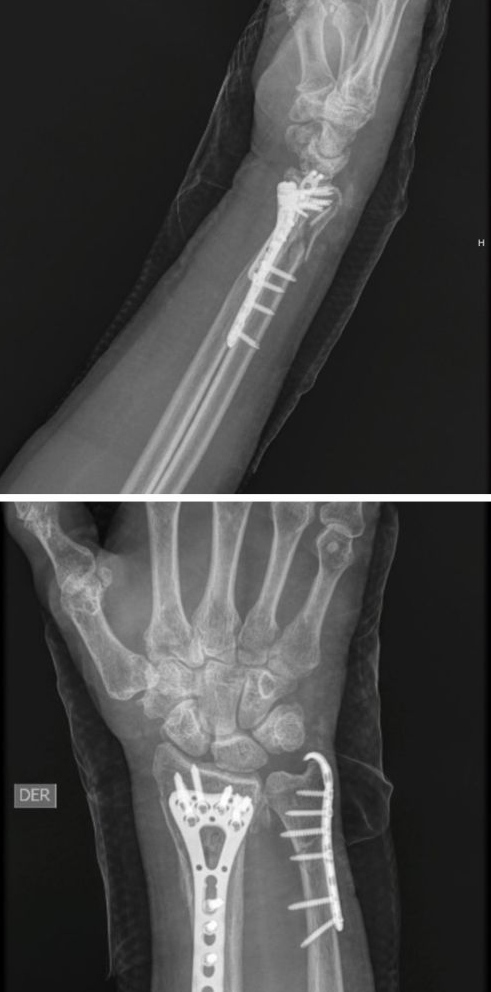

Antes

Después